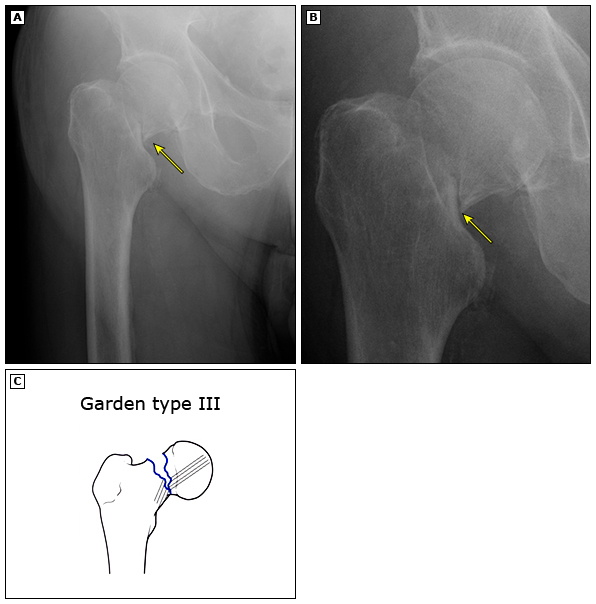

所谓「股骨颈」,就是连接股骨头和大腿骨的一段相对细小的骨头。下图就是股骨颈骨折的示意图。正如前文所说,老年人因为骨质疏松明显,只要跌倒大胯着地,就很容摔成这种骨折。

这个地方骨折很特殊。因为股骨颈一旦骨折,就很难再长好,尤其是对于老年人。

(2)复位打钉子固定

尽管也是做手术也要麻醉,但如下图所示,这种治疗是保留患者自己的骨头,在复位后用3枚钉子加压固定骨折断端,给骨折一个机会,希望它能自己长好。这种方法的优缺点如下: